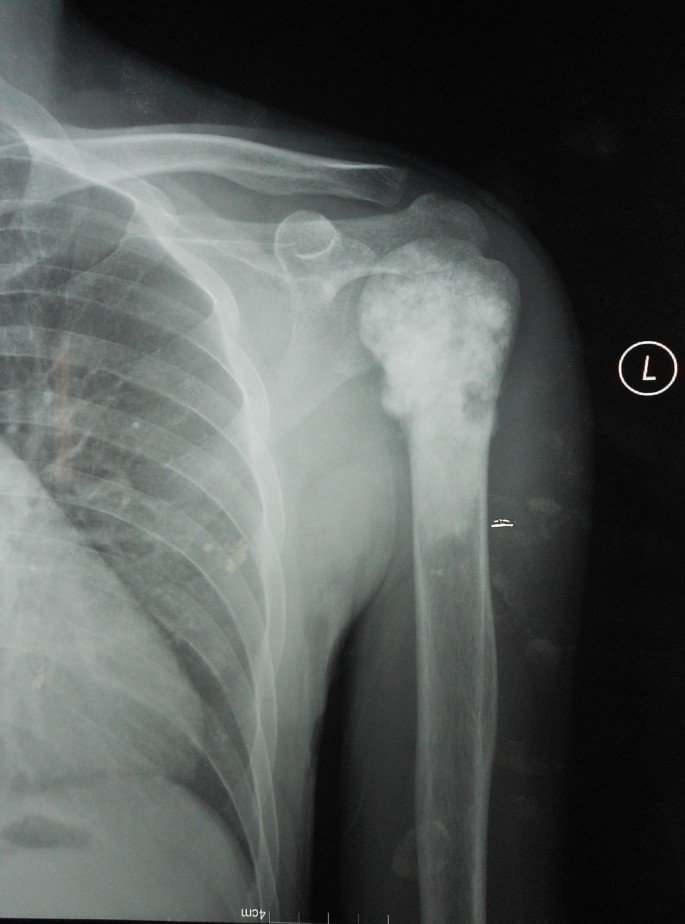

Рентгеновские снимки саркомы плечевого сустава